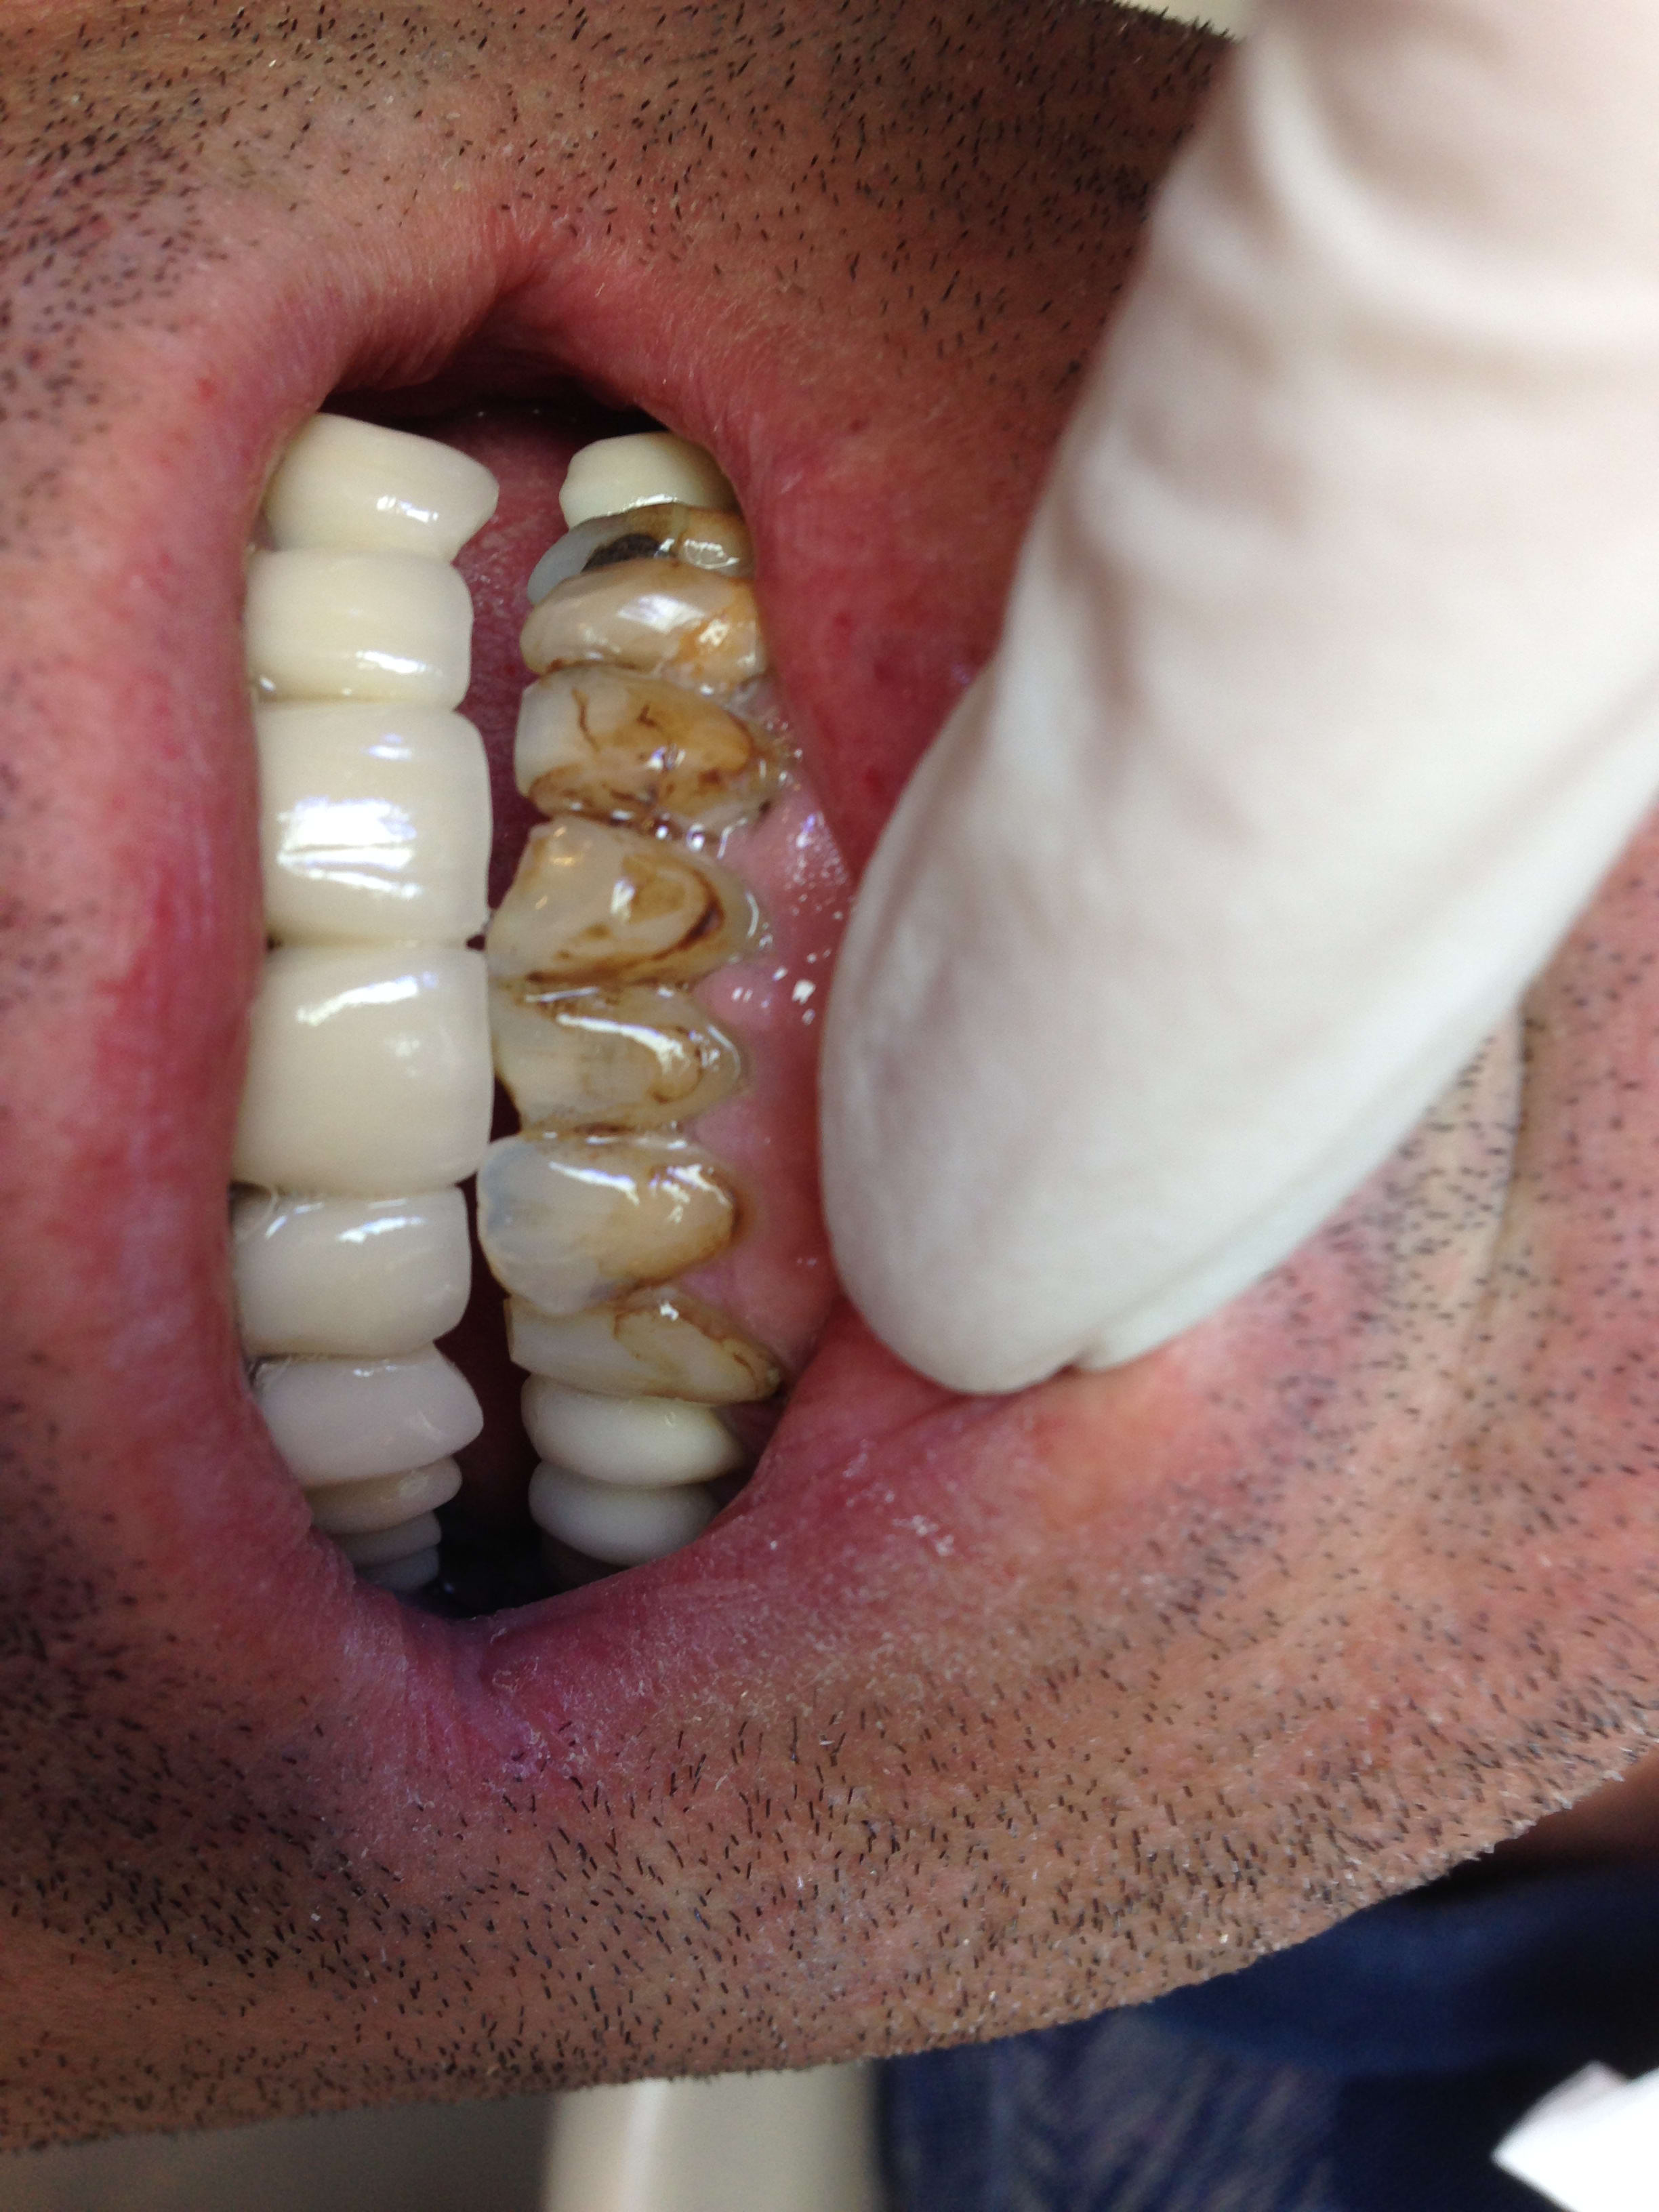

Regardez à la mandibule : c'était partout comme ça 😊

Img 1069 c1ckes - Eugenol